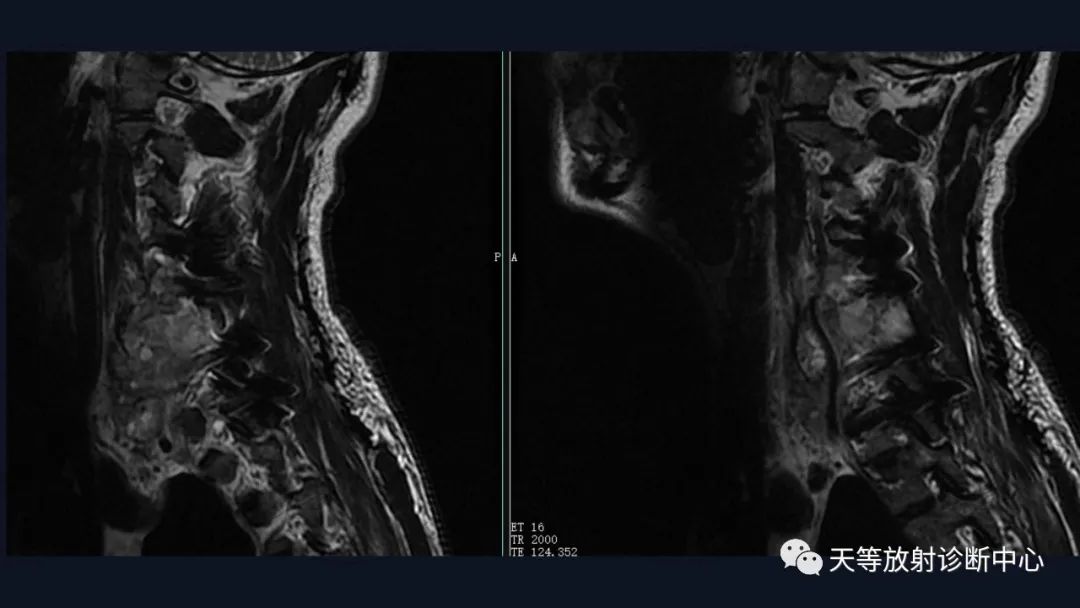

肿瘤复发,椎旁分叶状软组织肿块,内部信号不均,混杂信号,高低信号不等,内见线状小叶间隔。

DWI信号较高,内部钙化灶呈散在泥沙样低信号灶。

1、骨破坏区位于椎体及附件区,溶骨性骨质破坏;

2、外生生长并形成软组织肿块

3、破坏与软组织不成比例,钙化出现多,钙化呈泥沙样,点状、块状、不规则型 ;

4、局部破入椎管内。

5、可见骨硬化。